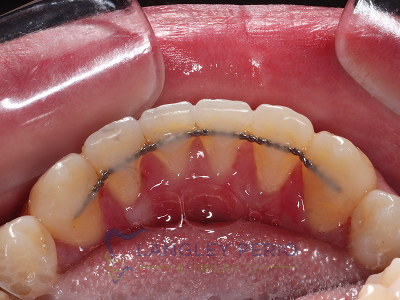

Case 2

Connective tissue grafting was done to cover exposed root surfaces to help to prevent root cavities from developing and reduce temperature sensitivity.